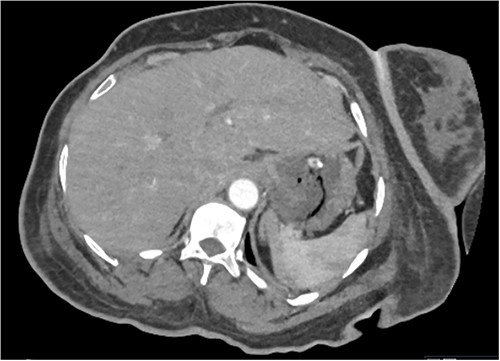

Based on the clinical and radiological picture, acute gastric dilatation was diagnosed, presumed secondary to a combination of opioid analgesia and gastric dysmotility from Parkinson’s disease. A nasogastric tube was introduced, intravenous fluids were given, and a venous blood gas was performed, which showed pH of 7.46 and lactate 1.0 mmol/L. An urgent CT scan of the abdomen and pelvis with intravenous contrast was performed; this demonstrated there had been interval reduction of the portal venous gas (Fig. 3), with only minor residual gas seen at the periphery of the left lobe of the liver and the gastric fundal wall. No other radiological features of visceral ischaemia within the abdomen were observed, with the coeliac axis and the collaterals from the phrenic arteries and superior mesenteric artery all patent.

CT abdomen and pelvis image demonstrating interval resolution of portal venous gas, at the level of T11/12.